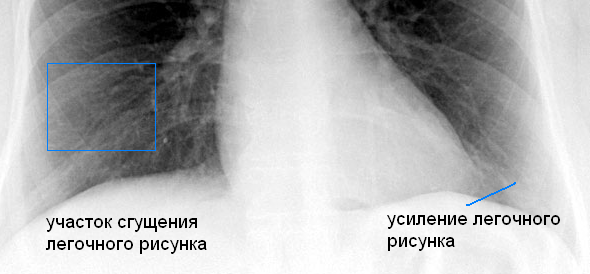

Фотографии, демонстрирующие обнаруженное усиление легочного рисунка

Раздел: Фотодневник открытий